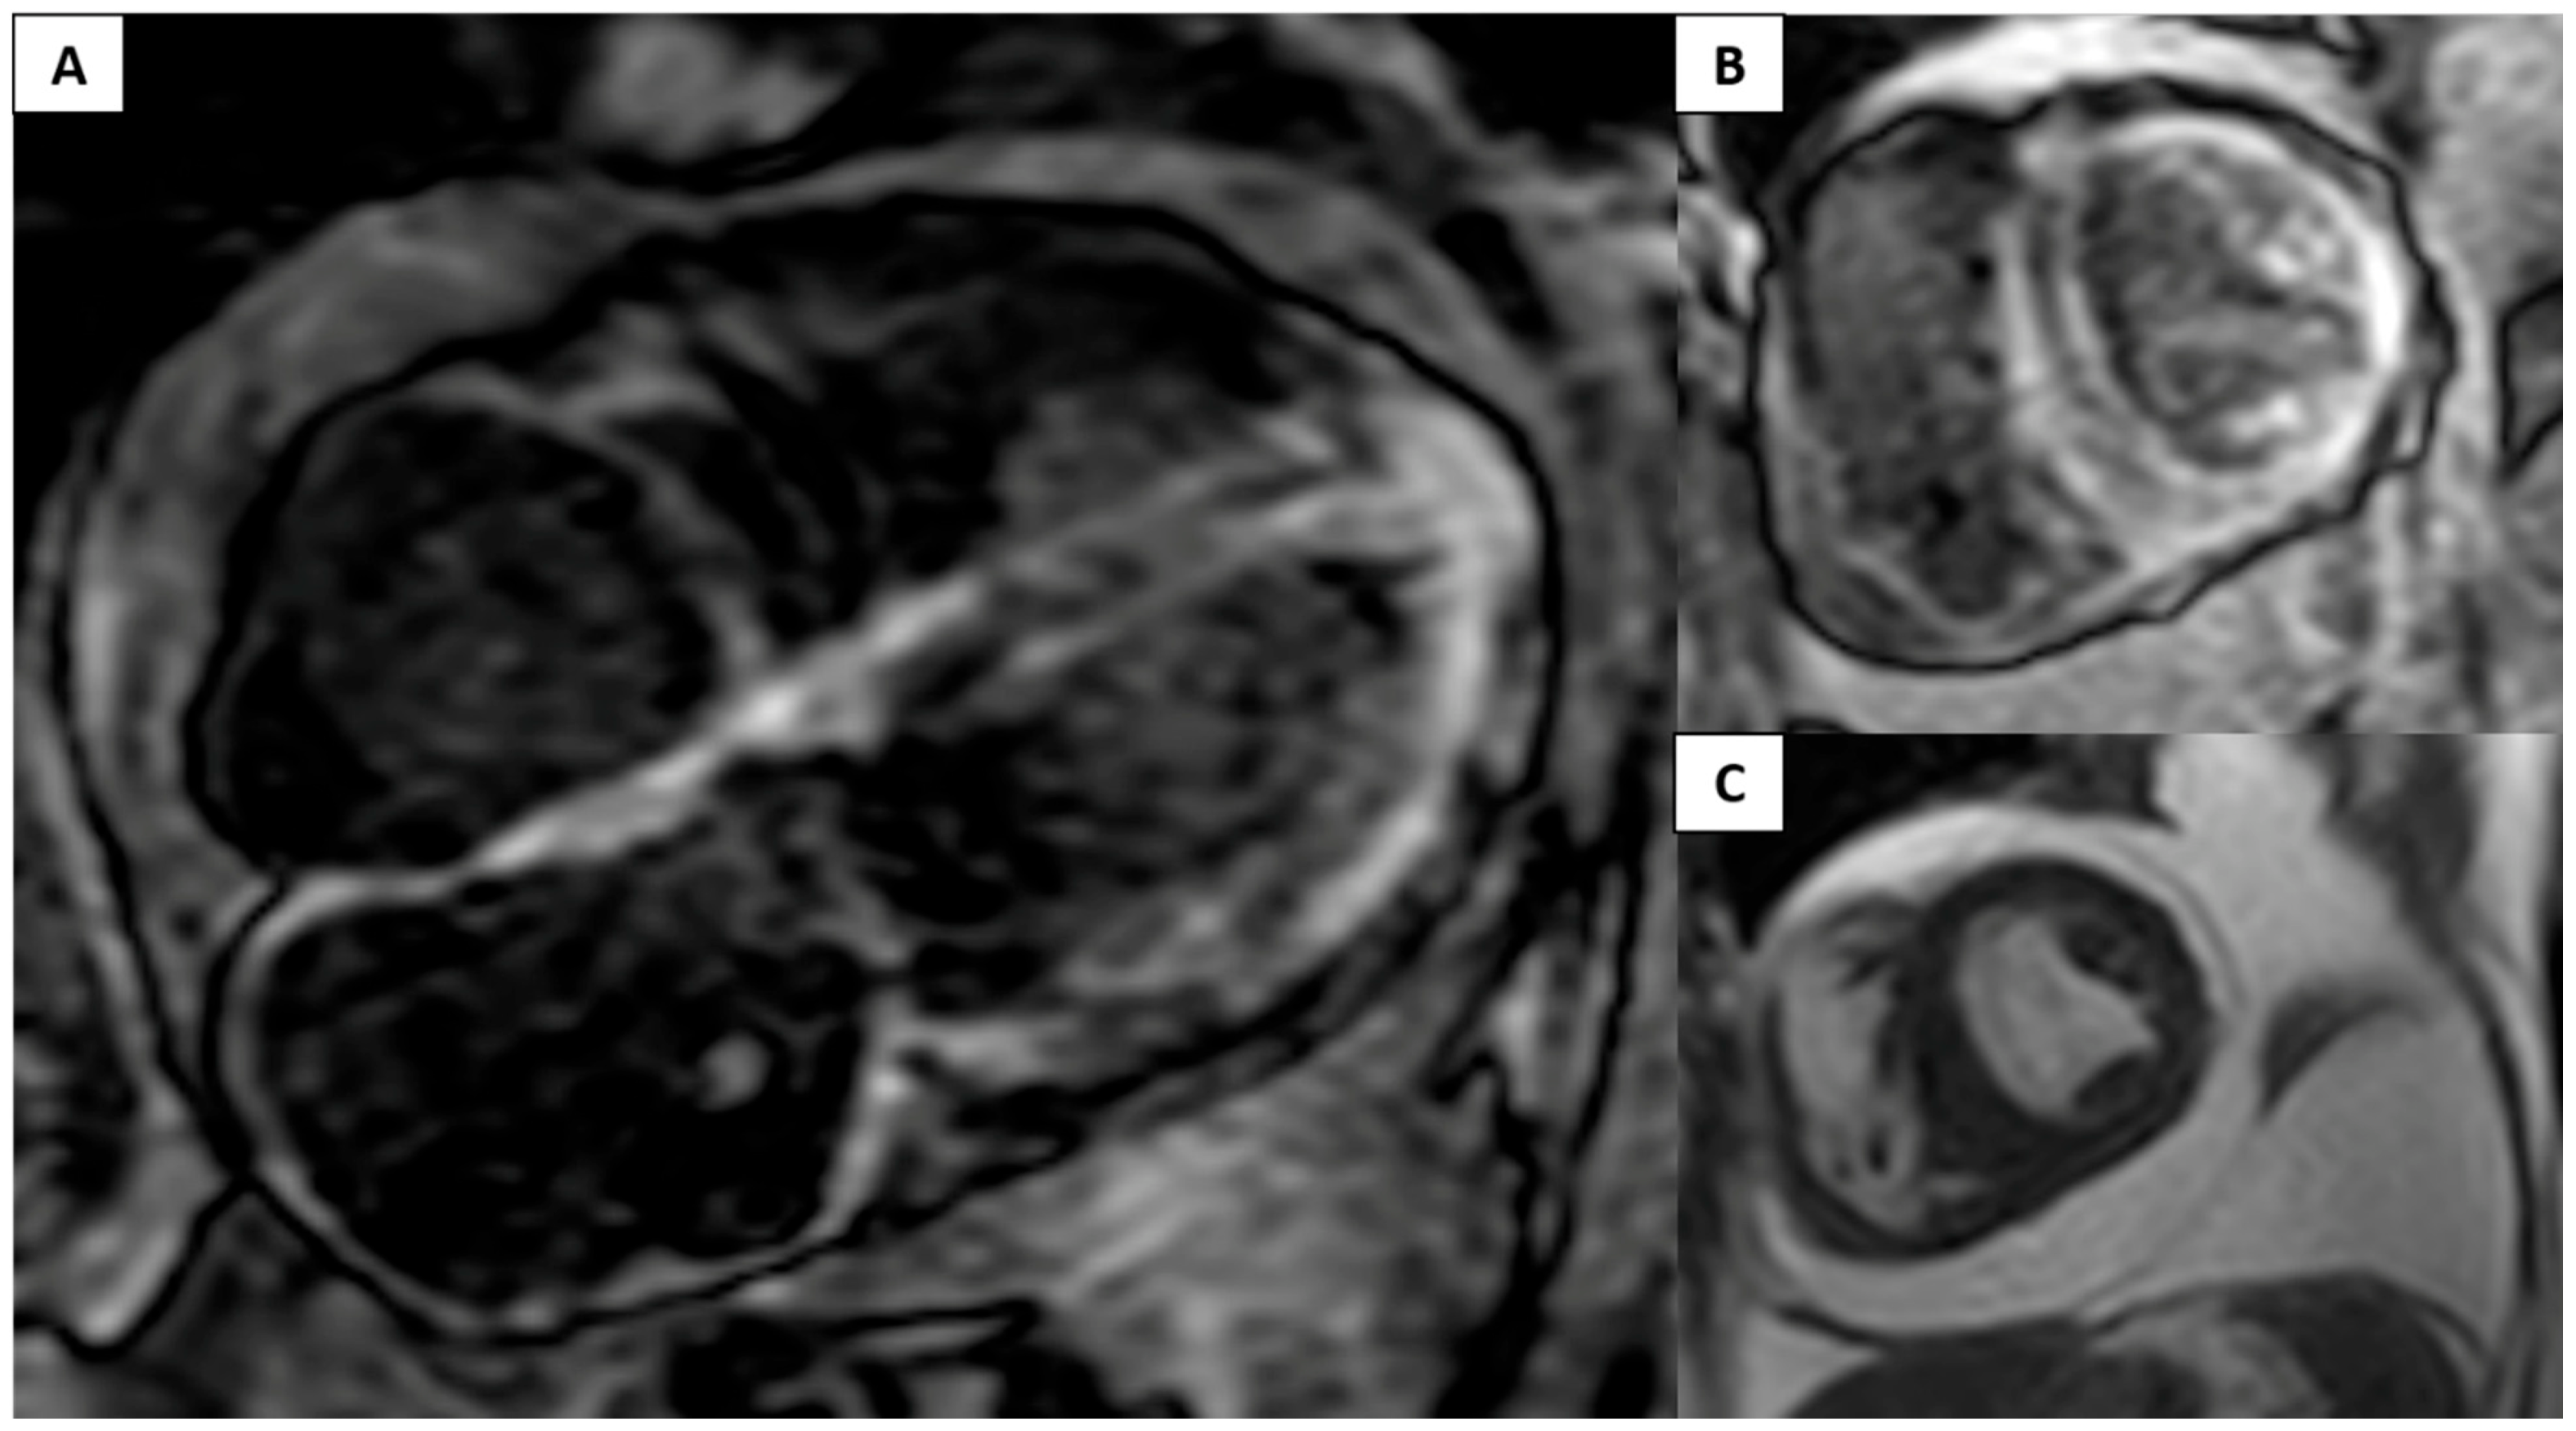

Clinical Case: Use of GBCAs in a Patient with Decreased Left Ventricular Ejection Fraction and Increased Thickness